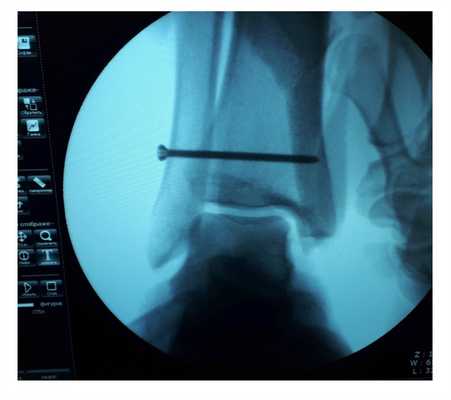

После восстановления латерального связочного комплекса по Брострому в модификации Голда и фиксации межберцового синдесмоза винтом производится оценка стабильности голеностопного сустава при помощи вальгус—стресс теста под контролем ЭОП.

Гипермобильность голеностопного сустава устранена, положение таранной кости остаётся неизменным несмотря на приложение вальгусной нагрузки.